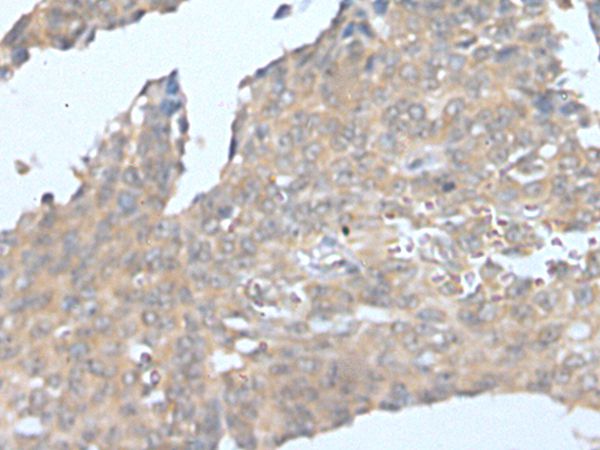

The image on the left is immunohistochemistry of paraffin-embedded Human ovarian cancer tissue using CSF1 Antibody at dilution 1/25, on the right is treated with synthetic peptide. (Original magnification: x200)